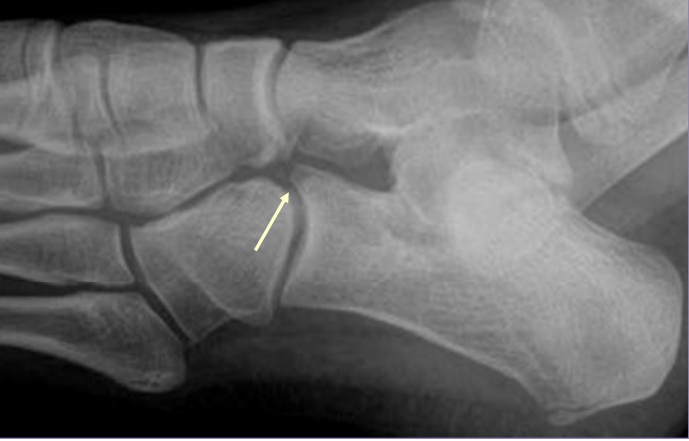

Est-ce que le bec du calcaneus c'est ça ? :